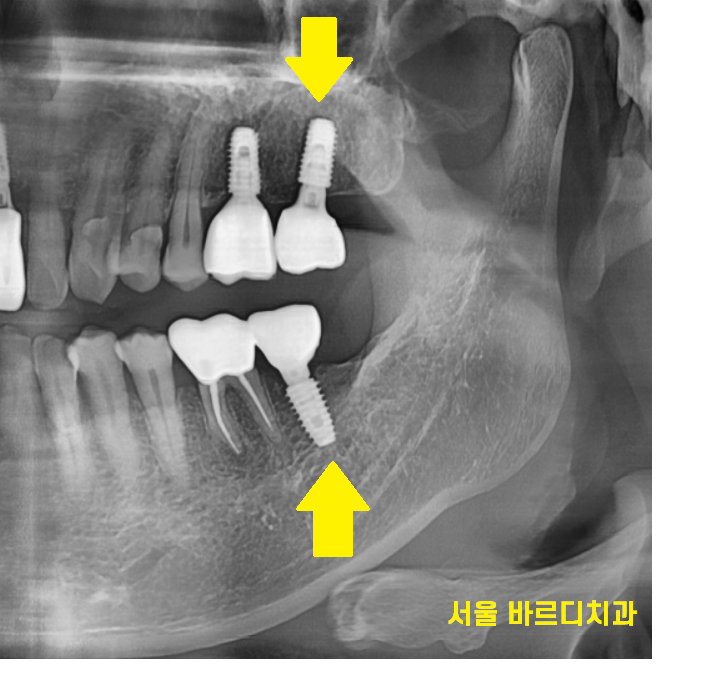

231227

없었던 큰 어금니 1개

보험 임플란트 덕분에 회복했습니다.

크기가 큰 놈이 두개나 더 생겼으니

오른쪽, 왼쪽 대칭감있게

이제 식사하시면 되겠네요~